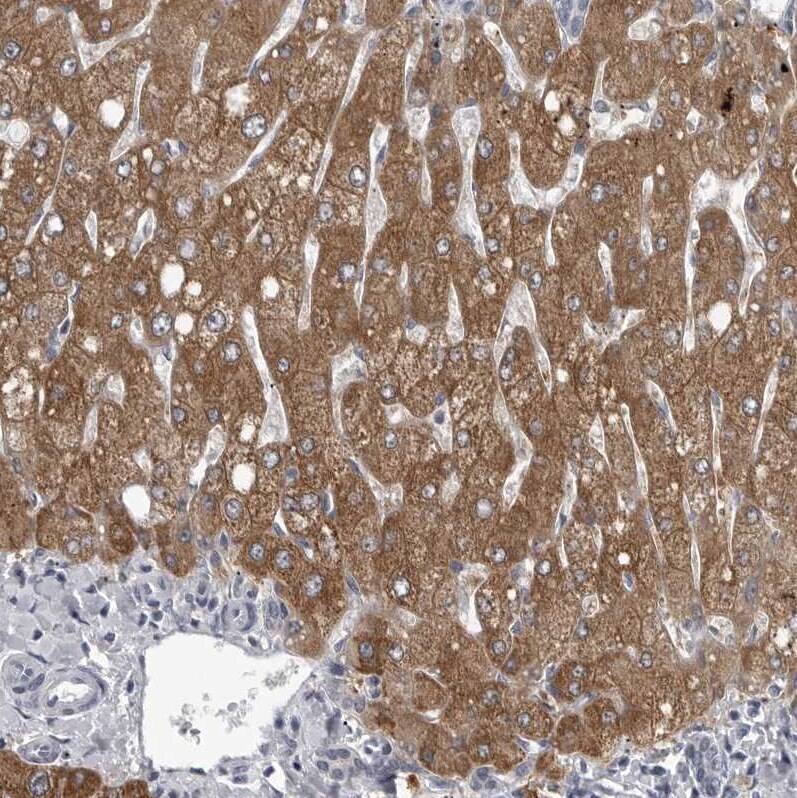

- Immunohistochemical analysis of LYSMD1 in human liver using LYSMD1 Polyclonal Antibody (Product # PA5-55755) shows moderate cytoplasmic positivity in hepatocytes.